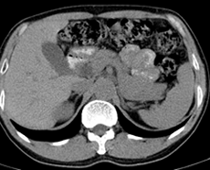

患者,男,57,常年不吃午饭,近一个月来腹部隐痛,无明显黄疸,明天进行增强扫描,图象另上传,麻烦各位帮忙一起看看讨论讨论

肝外胆管扩张,胰头增大,肠系膜上静脉似有包埋征象。

考虑:胰头占位性病变,建议增强进一步检查。

肝外胆管稍扩张,胰腺钩突略增大,但外形尚可,境界清楚。(常年不吃午饭)提示胰腺炎可能大,肿瘤第二步考虑。

支持考胰头占位性病变,感觉十二指肠壁不规则增厚,不排除十二指肠降部占位可炎症

胰头增大,胆总管增宽,考虑胰头癌可能性大,明天看增强片有助诊断.